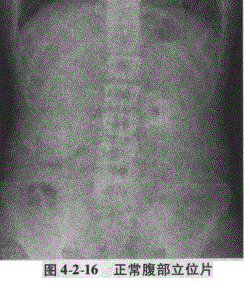

在清晰度良好的平片上,肝脏、脾脏的下缘及双肾的轮廓、腰大肌可见显示,胃肠道内的气体表现为形态不一的透亮影,结肠直肠内的粪便可因周围气体衬托而显示,呈团块状影,膀胱内尿液充盈时部分可显影(图4-2-16)。